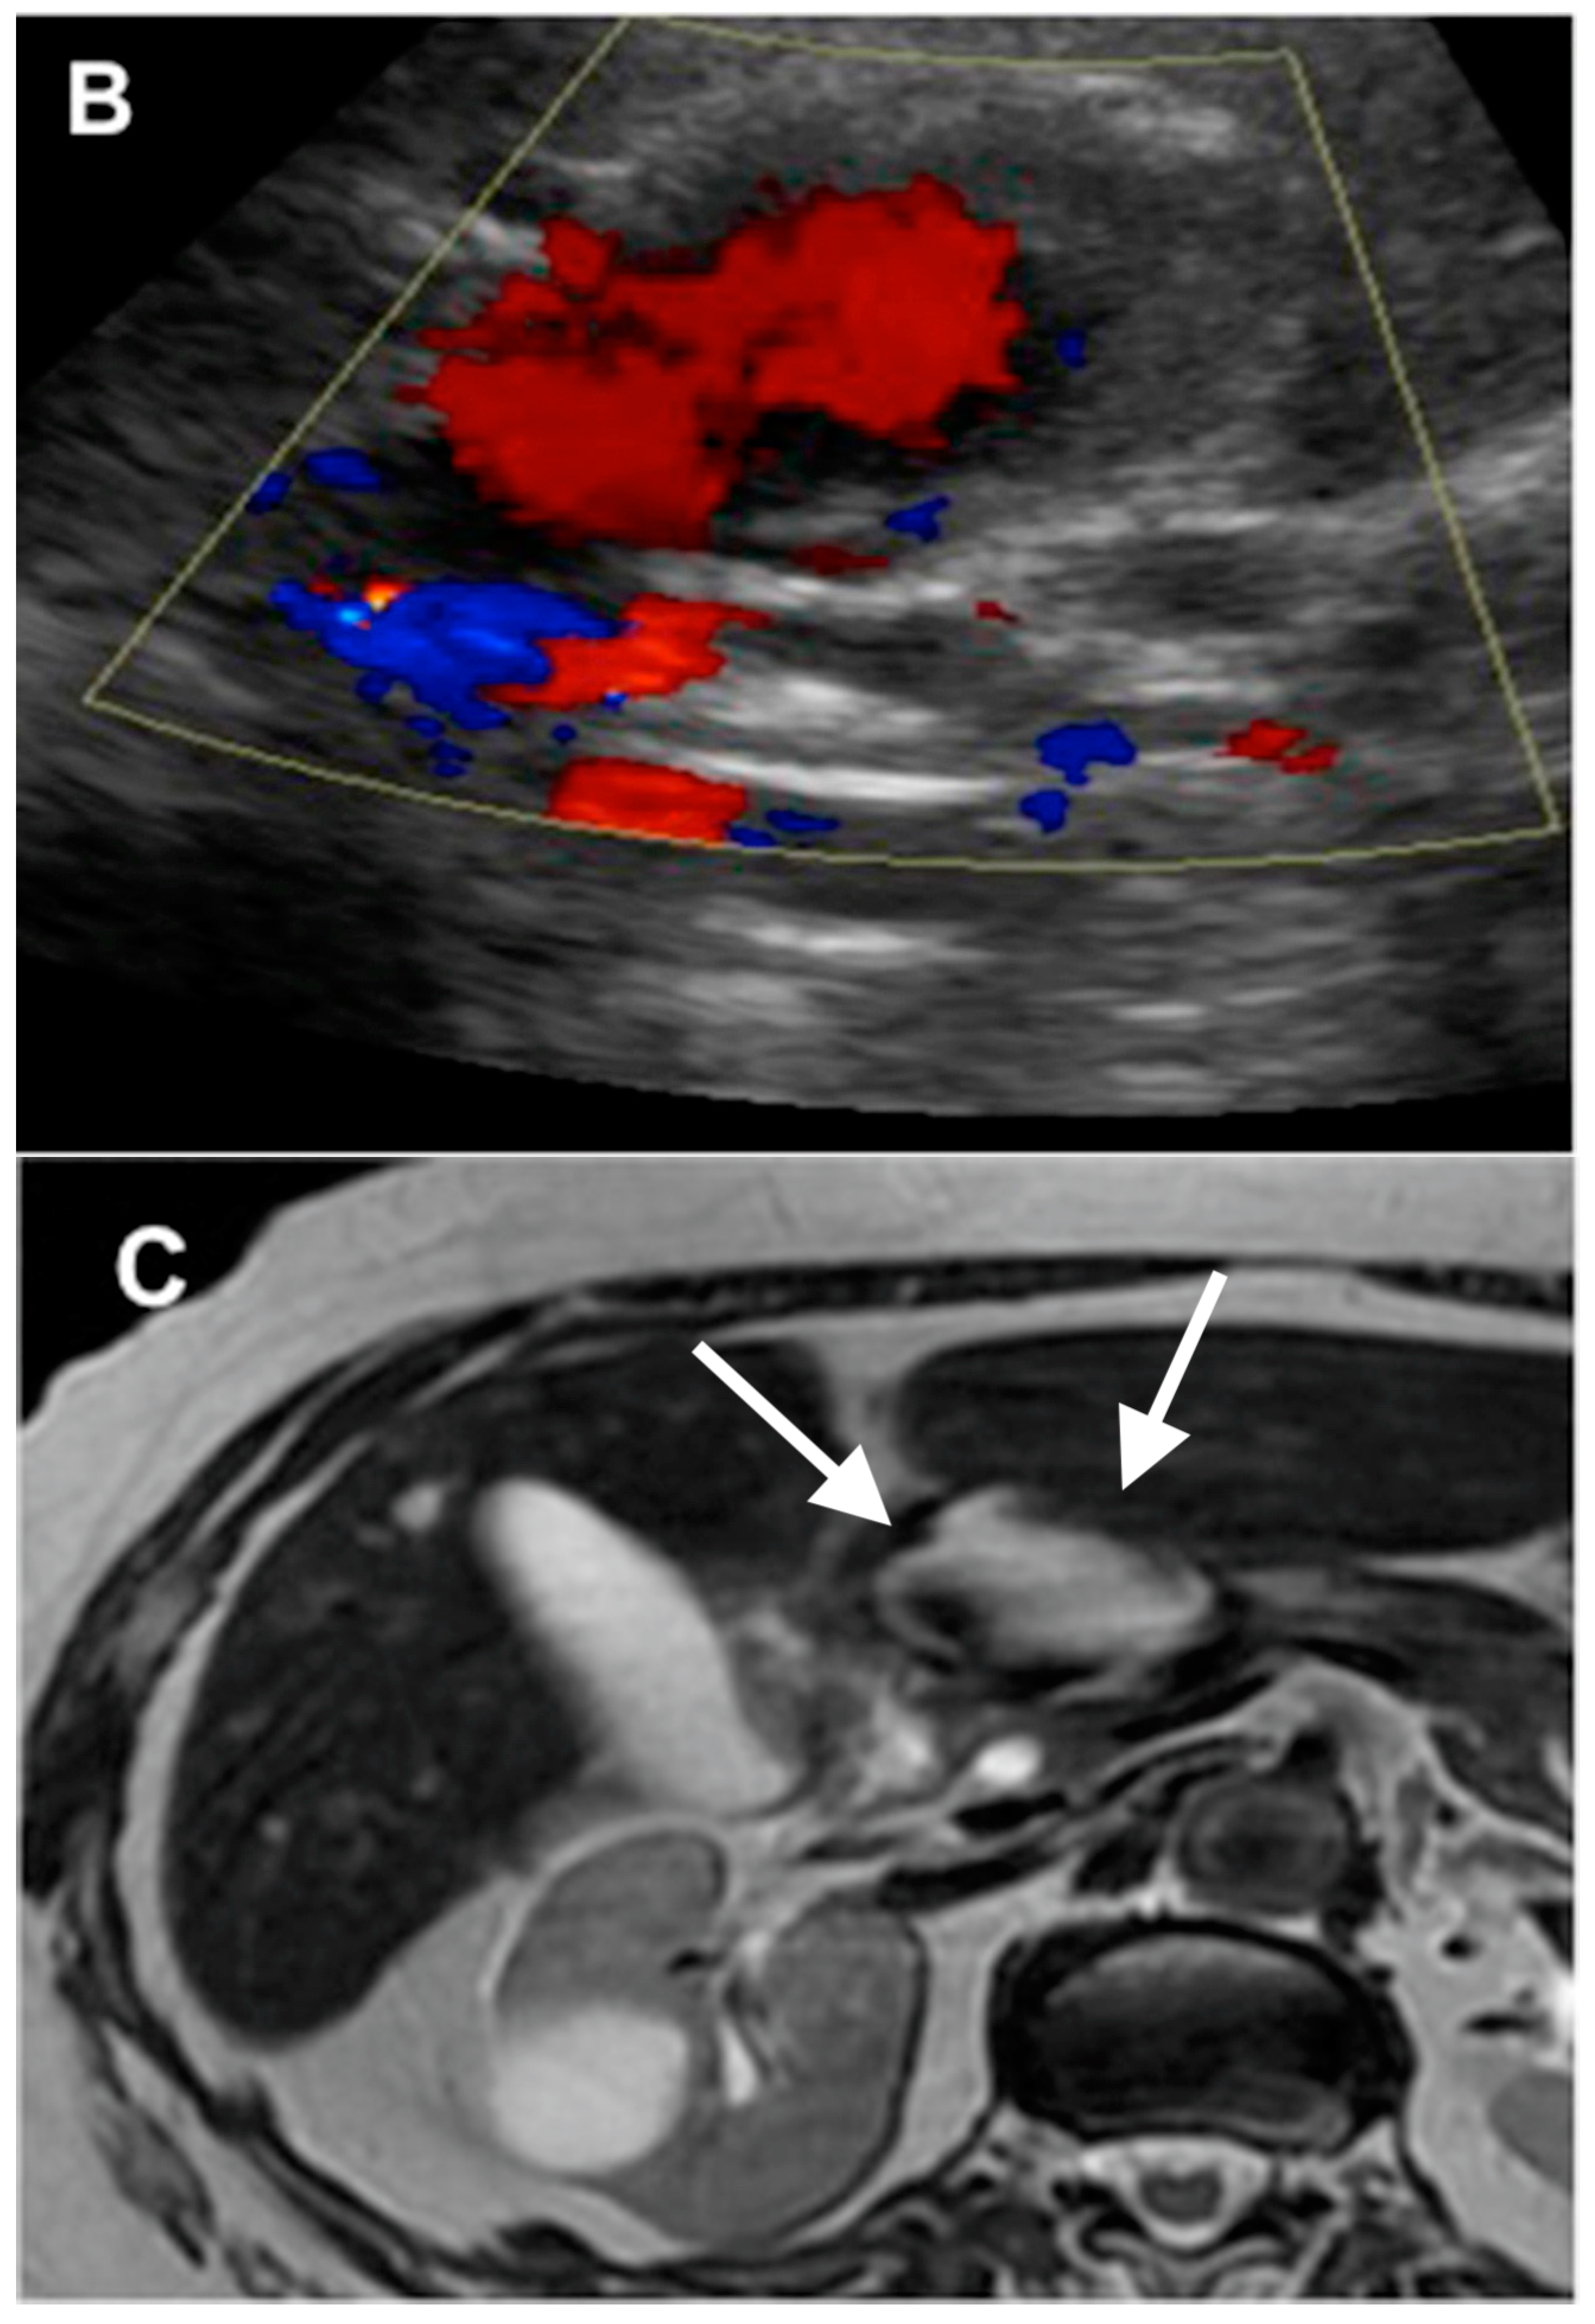

4. GDA Pseudoaneurysm Embolization